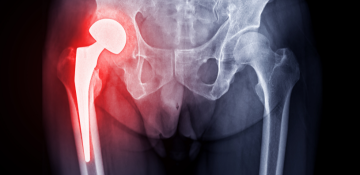

Αρθροπλαστική Ισχίου & Γόνατος

Αποκατάσταση φθαρμένων ή τραυματισμένων αρθρώσεων με σύγχρονες τεχνικές και εμφυτεύματα υψηλής ακρίβειας. Ιδανική λύση για ασθενείς με έντονο πόνο ή περιορισμένη κινητικότητα.